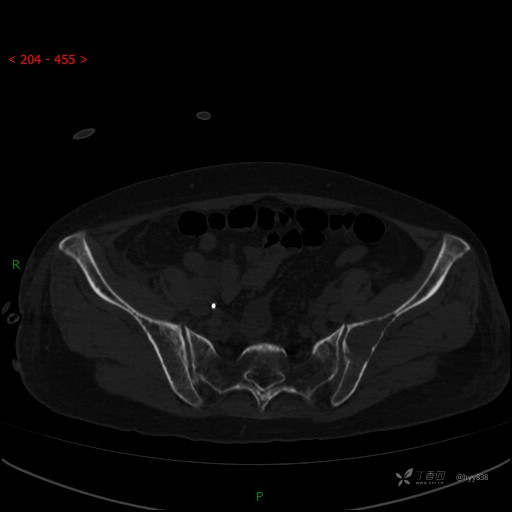

骨窗